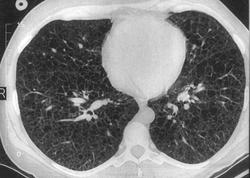

лимфангиолейомиоматоз

Типичный пример патологии при которой основным патерном являются кисты - :

Лимфангиомиоматоз.

Из архива AFIP. Лимфангиолейомиоматоз.

Лимфангиолейомиоматоз.